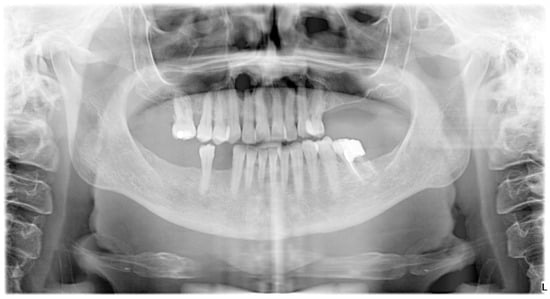

2. The Case